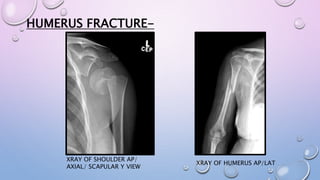

HUMERUS FRACTURE-

XRAY OF SHOULDER AP/

AXIAL/ SCAPULAR Y VIEW

XRAY OF HUMERUS AP/LAT

EARLY IMMOBILISATION- SHOULDER

IMMOBILISER, ARM SLING POUCH, U SLAB.